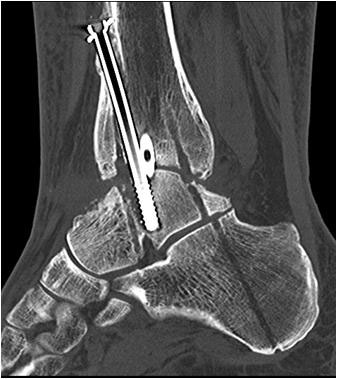

• Primäre oder posttraumatische Arthrose des OSG und USG (Abbildung 1, Abbildung 2).

• Revision einer gescheiterten Fusion des OSG/ USG (Abbildung 3, Abbildung 4).

• Pseudarthrosen (Abbildung 5, Abbildung 6).